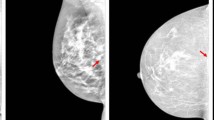

Deep learning-based segmentation has emerged as a powerful and effective technique for addressing diverse medical imaging tasks. Particularly, in mammography image analysis, segmenting the anatomical structures plays a significant role in computer-aided diagnosis assistance and positioning assessment. However, accurately identifying the pectoral muscle in the craniocaudal view presents challenges even for experienced radiologists due to its variable size, potential absence, and fibroglandular tissue overlaps. These challenges are further amplified when dealing with error-prone annotations, where mislabeled or inaccurately labeled data can lead to training the model on incorrect information. Consequently, this can cause the model to learn from these errors and produce underperforming or suboptimal results during inference. To address this, we propose a two-stage data-centric approach to enhance the accuracy of the deep-learning-based mammography segmentation model. In the first stage, we introduce a shape-based label analysis to automatically identify pectoral muscle labels with possible inconsistencies for a posterior manual review and correction. Then, in the second stage, we downsample the training dataset by removing outlier images with dubious annotations. The experimental results show the effectiveness of prioritizing training data quality and reliability. This approach significantly improved the model’s ability to detect and accurately segment the pectoral muscle.